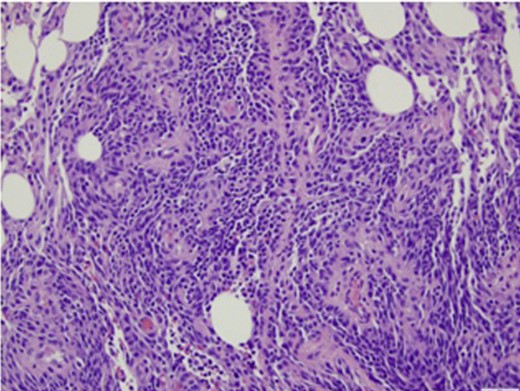

The final histopathology results of the omentum revealed high-grade angiosarcoma (Fig. 3). Due to his multiple co-morbidities, the patient was not a candidate for palliative chemotherapy. His clinical status continued to decline and he died 7 days post-operatively.

Histopathological analysis of formalin-fixed tissue sections of omentum showed diffuse involvement by a spindle cell neoplasm demonstrating both formation of vascular channels and solid areas of growth. Immunohistochemical stains (not shown here) were positive for CD31 and CD34. They were negative for cKit, DOG1, and keratins AE1/3 and cam5.2.

Typically, angiosarcomas have pathologic evidence of irregular vascular channels and mitotic figures. On microscopic examination of the omental specimen, there was diffuse spindle cell proliferation with prominent vascular channels in a background of necrosis and tissue hemorrhage. There were frequent mitoses observed. Immunohistochemical stains were positive for CD31 and CD34. The findings were consistent with high-grade angiosarcoma. The biopsy material of the peri-renal mass demonstrated totally necrotic tissue.